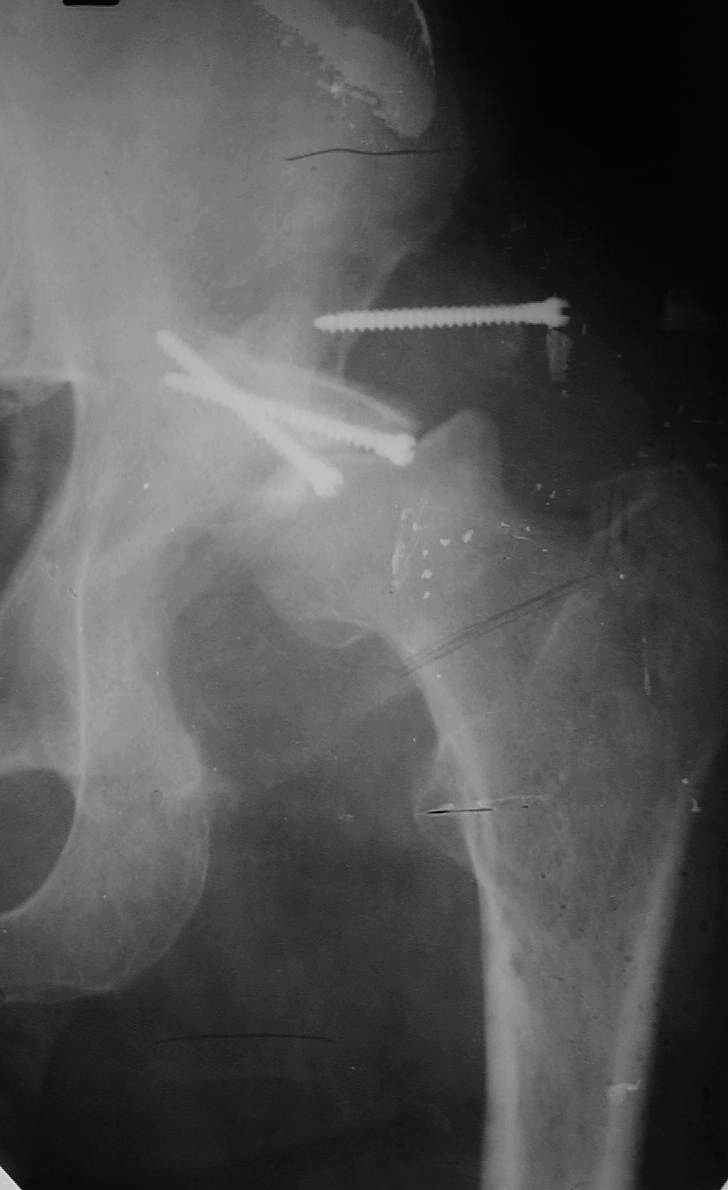

В институте совместно с фирмой Зиммер достаточно регулярно (практически ежемесячно) проводятся 2-х недельные циклы по различным вопросам эндопротезирования. Если есть возможность и желание, мы готовы поделиться с Вами нашим опытом, тем более есть что показать и что обсудить - в настоящее время ежедневно выполняется от 6 до 10 эндопротезирований коленного и тазобедренного сустава. В качестве примеров хочу показать 2 наблюдения, через 1 год и 5 лет после операции

1 год